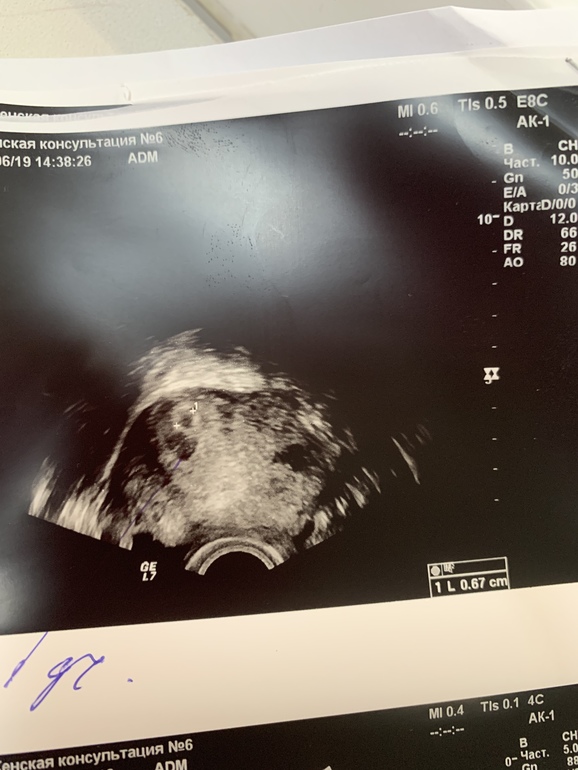

Образ жизни до, во время и после ЭКОДевочки, мамочки, всем привет! У меня сегодня 17 день ппэ, были 2 трехдневочки, хгч: 10 день-165, 12-423, 17-2351. Сходила на УЗИ, сказали отслойка, размеры 7,6 на 5,6, а плодное яйцо 6,7! Это очень много, верно? Моя репролуктолог в отпуске, была у врача по бесплодию, та сказала, что такое бывает и переживать не стоит! У кого была похожая большая отслойка? Чем закончилось? Как лечились?